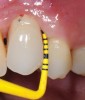

Preventive protocols must be instituted immediately after the installation of the definitive prosthesis and must focus on the importance of plaque control, both patient self-plaque control by strict home-based oral-hygiene practices and professional mechanical biofilm debridement at regular professional interventions, which must be customized to the patient’s risk profile.8 The efficacy of oral hygiene practices will depend on the ease of access to plaque control with both dental brushes and interdental devices, which depends mainly on the design of the prosthesis (Figure 6 through Figure 8). A cleansable implant-supported restoration, therefore, becomes a key factor in the primary prevention of peri-implant diseases. A recent systematic review on the efficacy of mechanical self-performed oral hygiene of implant-supported restorations reported a slight trend of superiority with the use of powered toothbrushes compared with manual.14

Fig 6. Customized oral hygiene to the implant-supported restoration with use of interdental brush;

Figure 6

Fig 7. use of gauze under the pontic.

Figure 7

Fig 8. use of gauze at the interdental space.

Figure 8